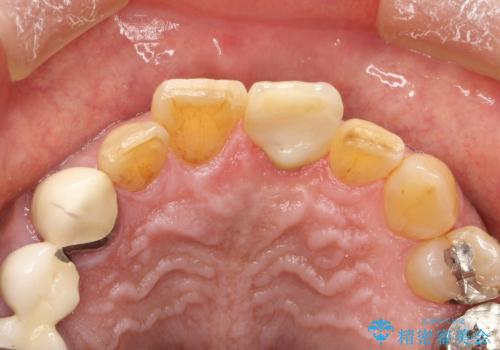

左上1が水平的に割れている状態で、歯冠を取り除くと神経が露出しており、唇側はかなり歯肉縁下で破折しており、そのままではかぶせものを入れるのは難しい状態でした。

抜かずになるべくその歯を残して使っていきたいとのことで、

根管治療をした上で歯を引っ張りだして(エクストリュージョン)、その後、骨外科にて歯周組織を整えた上で、かぶせものを入れていく治療計画をたてました。